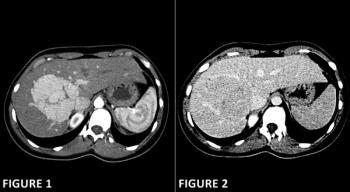

A 68-year-old woman is undergoing staging scans for gastric cancer. An image from her CT shows an abnormality. What is the diagnosis?